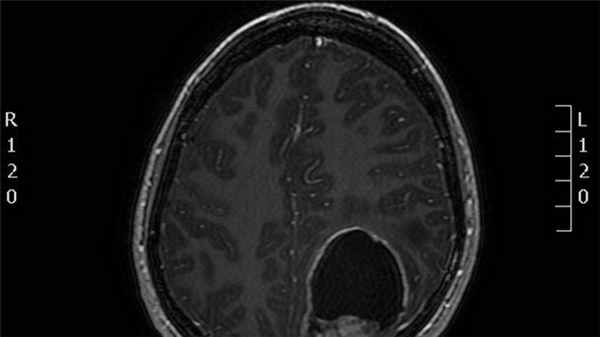

КТ/МРТ : обычно обнаруживают объемное образование в дне IV желудочка, часто с окклюзионной ГЦФ. Рентгенологически может быть трудно отличить от медуллобластомы (МБС); могут помочь следующие признаки:

- калицификаты часто встречаются в эпендимомах, но редко ( <10%) в МБС

- МБС: обычно возникают из крыши IV желудочка (из его вершины, фастигиума), который покрывает опухоль («симптом банана»); сравните с эпендимомами, которые имеют тенденцию врастать в IV желудочек со дна

- эпендимомы (в отличие от МБС) имеют негомогенную структуру на МРТ в Т1 режиме

- экзофитный компонент в эпендимомах имеет тенденцию давать высокий сигнал на МРТ в Т2 режиме (у МБС он только немного гиперинтенсивный)

Большинство эпендимом головного мозга (60%) локализуются в задней черепной ямке (инфратенториально), возникая в области дна 4го желудочка, особенно у детей 7. В остальных случаях (40%) локализуясь супратенториально составляют вплоть до половины интрапаренхиматозных случаев [7].

Эпендимомы задней черепной ямки обладая пластичностью распространяются через отверстия Лушка и Мажанди. Данный признак может быть визуализировать при КТ и МРТ.

Эпендимома обычно представлена гетерогенным образованием с зонами некроза, кальцинатами, кистозной трансформацией и зачастую кровоизлияниями.

- T1

- солидный компонент эпендимомы обычно имеет изо- или гипоинтенсивный сигнал по отношению к белому веществу [7]

- гиперинтенсивный сигнал по отношению к белому веществу

- является более надежной последовательностью в дифференциально диагностике опухолевого поражения, чем бесконтрастные Т1 ВИ (но менее надежные чем Т1 с парамагнетиками)

- фокусы цветения за счет кровоизлияния или кальцификатов

- гетерогенное усиление

Обычно обнаруживают объемное образование в дне IV желудочка, часто с окклюзионной гидроцефалией.

Рентгенологически может быть трудно отличить от медуллобластомы, могут помочь следующие признаки:

1. Калицификаты часто встречаются в эпендимомах, но редко (<10%) в медуллобластомах

2. Медуллобластомы обычно возникают из крыши IV желудочка (из его вершины, фастигиума), который покрывает опухоль («симптом банана»), эпендимомы имеют тенденцию врастать в IV желудочек со дна

3. Эпендимомы имеют негомогенную структуру на МРТ в Т1 режиме

4. Экзофитный компонент в эпендимомах имеет тенденцию давать высокий сигнал на МРТ в Т2 режиме (у медуллобластом он только немного гиперинтенсивный)